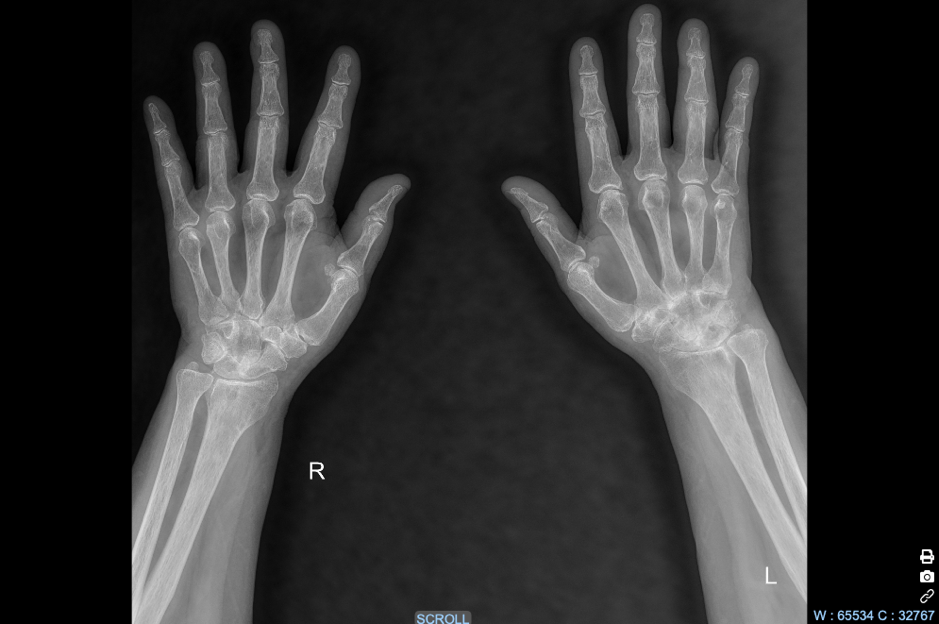

A 48-year-old woman comes to the physician because of a 11-month history of joint pain and stiffness in her wrists and fingers. The symptoms are worse in the morning and improve with activity after 2 hours. Physical examination shows swelling and warmth over the MCP and wrist joints in both hands. An Х-ray of the hands is shown. Synovial biopsy from an affected joint would most likely show which of the following?

D. Proliferation of granulation tissue

This patient has evidence of advanced rheumatoid arthritis, based on the findings of marginal erosions on imaging. Microscopic evaluation of a synovial biopsy would most likely show granulation tissue with mononuclear cells, also referred to as pannus. Synovial fluid analysis in this patient would be expected to show neutrophilic infiltrate, increased proteins, reduced viscosity, and possibly rheumatoid factor.